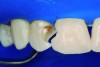

The partial pulpotomy was performed for tooth No. 7 due to the pulp exposure during the caries removal procedures (Figure 5). The superficial contaminated pulp tissue was removed with a No. 1012 spherical diamond bur at high speed with water cooling to allow a better reparative response. This procedure was limited to removal of the infected dentin and damaged pulp tissue, removing the injured odontoblast cell layer. During this step, the remaining pulp tissue was analyzed and found to have good consistency and abundant red bleeding (Figure 6). After the pulpotomy, a solution of calcium hydroxide was used for irrigation along with a sterile cotton pellet to achieve hemostasis and disinfection. After hemostasis, the tooth was treated with direct pulp capping: the exposed area was covered with calcium hydroxide powder (Figure 7) and calcium hydroxide cement (Figure 8). The cavity was provisionally restored with the use of a restorative GIC (Figure 9).

Fig 5. Partial pulpotomy with No. 1012 diamond bur under water cooling.

Figure 5

Fig 6. Aspect of the pulp after partial pulpotomy, showing the abundant red bleeding.

Figure 6